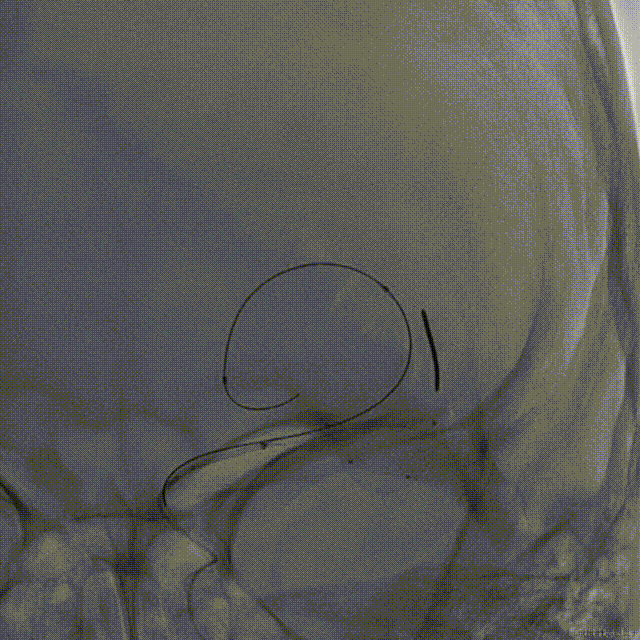

释放弹簧圈:

支架释放后,使用弹簧圈微导管释放弹簧圈,填塞动脉瘤。

术后即刻造影

术后即刻造影,正侧位造影示载瘤动脉血流通畅,各主要分支血管显影良好,瘤腔内未见造影剂残余。